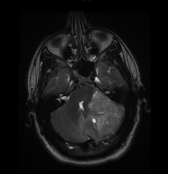

MRI3 January 23, 2015 By Gari Share this:TweetShare on Tumblr Email a link to a friend (Opens in new window) Email More Share on Reddit (Opens in new window) Reddit Print (Opens in new window) Print Like Loading... About Gari Northern lad; living out in the Peak District and rediscovering life after having had a brain tumour.